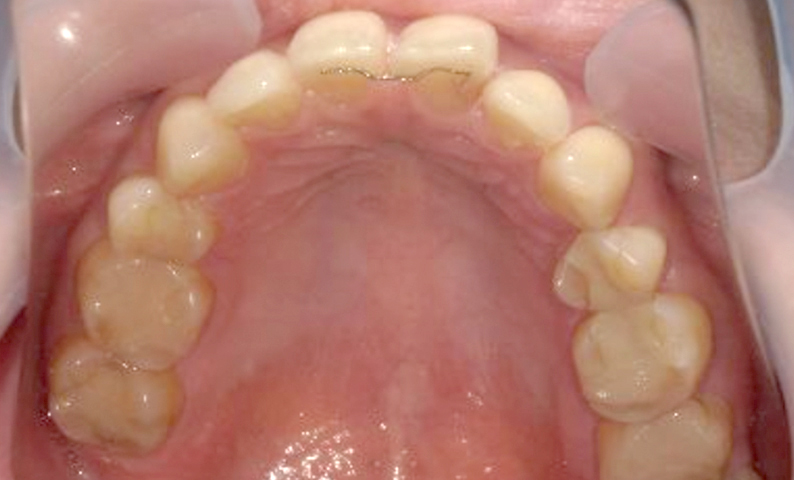

| 治療前 | 治療後 |

|---|---|

|